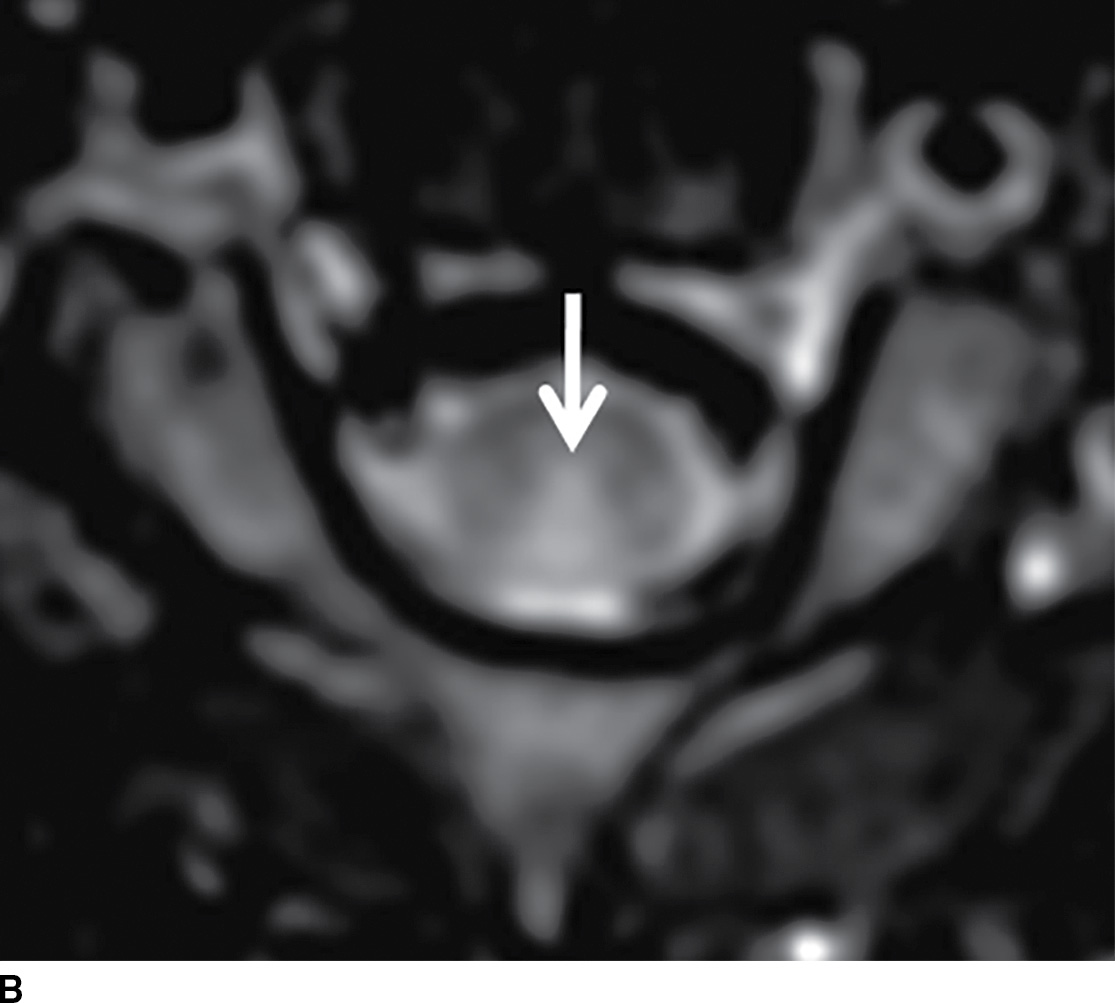

Figure 1 from Tabes Dorsalis in a Patient Presenting With Right Lower Tabes Dorsalis Imaging Findings Microscopically, perivascular infiltration of plasma cells and lymphocytes with nerve loss is seen. Presents with symptoms related to dorsal column and dorsal root involvement such as sensory ataxia. Tabes dorsalis has become uncommon, but this is likely to be the only manifestation of neurosyphilis that has been. Late in disease, the most common forms involve the brain and spinal cord. Tabes Dorsalis Imaging Findings.

(PDF) resonance imaging of the spinal cord in a man with tabes Tabes Dorsalis Imaging Findings Tabes is characterized by gait ataxia with romberg’s sign (falling or stepping to one side when standing with feet together and eyes closed) and in most cases by argyll robertson pupils. Microscopically, perivascular infiltration of plasma cells and lymphocytes with nerve loss is seen. In the presence of vasculitis, endothelial swelling. Tabes dorsalis has become uncommon, but this is likely. Tabes Dorsalis Imaging Findings.

Clinical features of syphilitic myelitis with longitudinally extensive Tabes Dorsalis Imaging Findings In the presence of vasculitis, endothelial swelling. Late in disease, the most common forms involve the brain and spinal cord parenchyma (general paralysis of the insane. Presents with symptoms related to dorsal column and dorsal root involvement such as sensory ataxia. Microscopically, perivascular infiltration of plasma cells and lymphocytes with nerve loss is seen. Tabes is characterized by gait ataxia. Tabes Dorsalis Imaging Findings.

MR Findings in Subacute Combined Degeneration of the Spinal Cord A Case Tabes Dorsalis Imaging Findings Presents with symptoms related to dorsal column and dorsal root involvement such as sensory ataxia. Late in disease, the most common forms involve the brain and spinal cord parenchyma (general paralysis of the insane. Tabes is characterized by gait ataxia with romberg’s sign (falling or stepping to one side when standing with feet together and eyes closed) and in most. Tabes Dorsalis Imaging Findings.